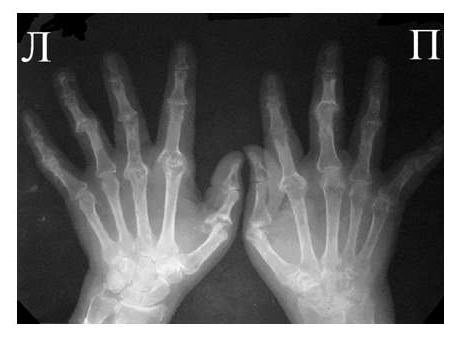

Рис. 3 Сочетание ревматоидного артрита и остеоартроза

Большинство ошибок встречаются при начальных стадиях, особенно при начале РА в пожилом возрасте и сочетании его с остеоартрозом (см. рис. 3). В этом случае для подтверждения диагноза РА и предупреждению случаев его гипердиагностики служит выявление симметричных эрозий в типичных для ревматоидного артрита суставах (запястья, плюснефаланговые, пястно-фаланговые).